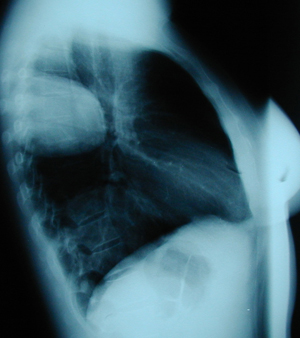

Εικόνα 2

Πλάγια ακτινογραφία θώρακος. Διακρίνονται δύο μεγάλες κύστες εχινοκόκκου, μια στο άνω λοβό και η άλλη στο κάτω λοβό.